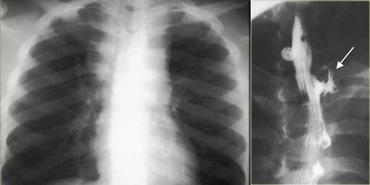

TRÁI: Thực quản giãn (mũi tên) biểu hiện là cấu trúc dài, bờ rõ nét song song với tim. PHẢI: Thực quản giãn thường lệch sang phải. Hẹp (mũi tên) tại khe hoành.

Achalasia

- Biểu hiện lâm sàng:

- Tỷ lệ mắc bệnh bằng nhau ở nam và nữ, thường gặp nhất ở độ tuổi trung niên

- Khó nuốt tiến triển chậm

- Tăng nguy cơ ung thư

-

Căn nguyên:

- Chưa rõ, mặc dù số lượng tế bào hạch thực quản bị giảm

- Cơ thắt thực quản dưới (LES) giãn không hoàn toàn hoặc không giãn khi nuốt

- Mất sóng nhu động nguyên phát

Hình ảnh chụp thực quản:

- Giãn thực quản kèm mất nhu động

- Hẹp thuôn nhẵn tại khe thực quản của cơ hoành

- Ung thư đoạn xa có thể giả dạng achalasia (giả achalasia)